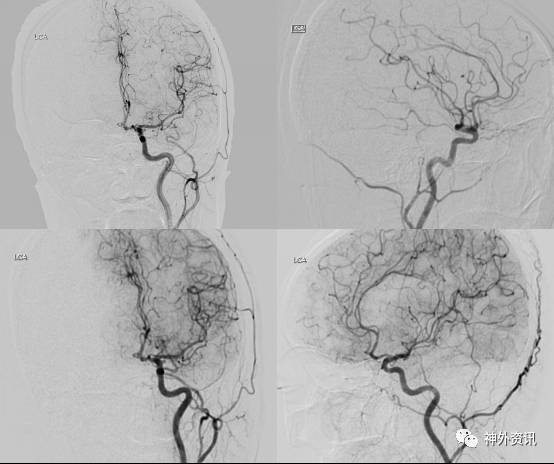

术前CTA(2017-03-28): 左侧颈内动脉虹吸部、左侧大脑前动脉A2段管壁多发小动脉瘤

术前DSA(2017-03-24):左颈内动脉后交通段、左侧颈内动脉眼动脉段、大脑前动脉A1段多发动脉瘤